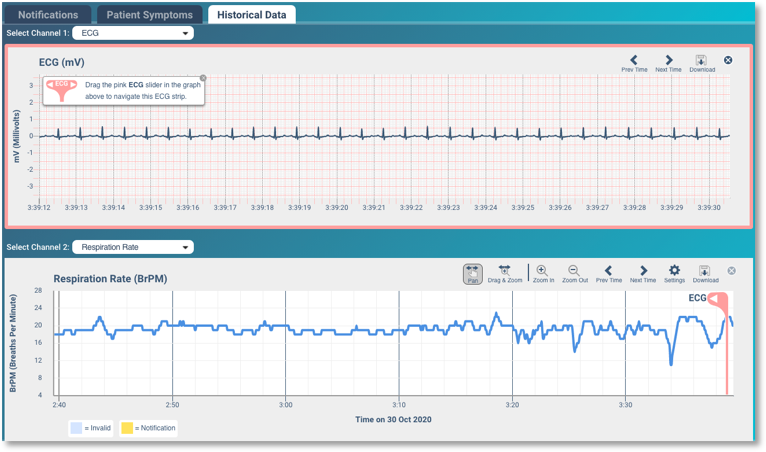

For those already diagnosed with respiratory illness, advancements in remote monitoring and telehealth are fundamentally reshaping how and where prevention happens. Wearable biosensors such as Strados RESP and VitalPatch can now capture cough frequency, lung sounds, oxygen saturation, and breathing patterns continuously and in real time. This data gives clinicians early warning of changes in a patient’s condition and allows them to intervene before symptoms become severe — reducing emergency visits and hospitalizations. Similarly, remote spirometry tools make it possible for patients with asthma or COPD to conduct lung function tests at home. Providers can review the results asynchronously or in virtual visits, adjusting treatment plans proactively instead of reactively.